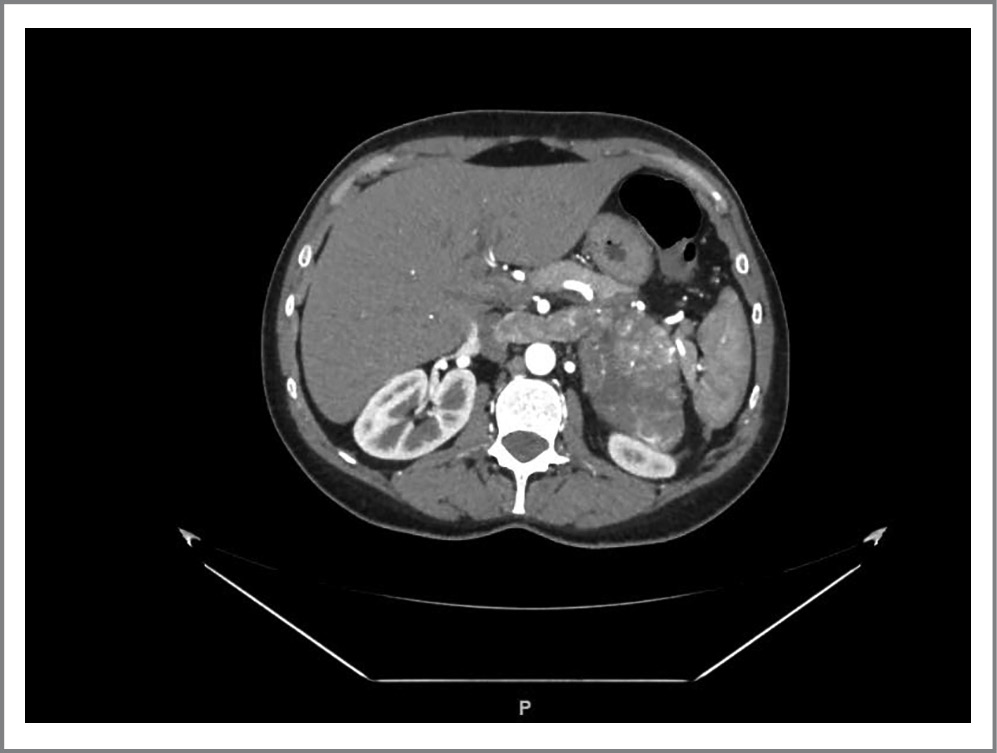

В ходе госпитализации выполнен пересмотр предоставленных дисков МСКТ. На исследовании от 20.09.2018 размеры образования составляли 4,8×6,5×5,5 см, однородной структуры, плотностью около 36 HU. На исследовании от 03.10.2019 выявлен рост образования до 6,8×8,9×8,3 см с включениями кальцинатов. Контрастные характеристики опухоли по фазам сканирования: артериальная-венозная-отсроченная 94–77–60 HU. По нижнемедиальному контуру образования визуализируется образование размерами 2,9×2,0×2,2 см, которое не определялось на исследовании от 20.09.2018 (рис. 3).

Рис. 3. МСКТ от 03.10.2019.

Fig. 3. Multispiral computed tomography data (October 3, 2019).